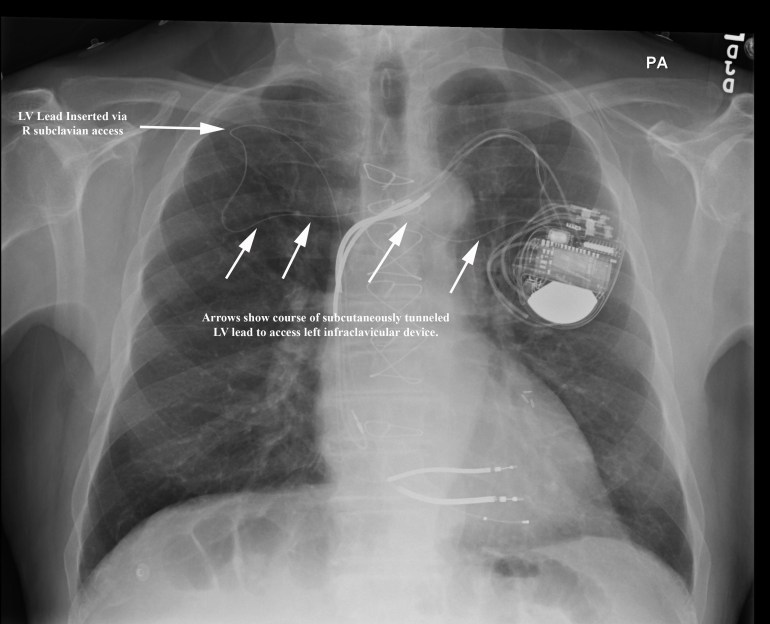

Given the patient’s extreme age, the decision was made not to attempt opening his chronic left subclavian venous occlusion or attempt laser lead extraction of the abandoned RV lead. We opted to place a coronary sinus LV lead via a patent right subclavian vein and percutaneously tunnel the lead to his existing left sided device. A 2cm incision was made in the right infraclavicular region and LV lead was placed without difficulty in a posterolateral branch of the coronary sinus. This lead was anchored to the right prepectoral fascia then tunneled subcutaneously to the exisiting left infraclavicular lead system. Tunneling was performed without incident and the patient underwent a successful upgrade to a biventricular defibrillator. The figure below depicts the chest xray and course of the tunneled LV lead. There was minimal postoperative discomfort along the course of the tunneled lead.